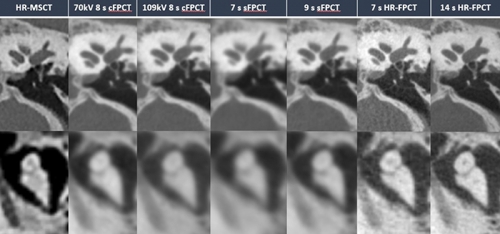

Figure 1

Illustrative example of the different protocols in the visualization of middle ear landmarks, stapes (top row) and incudomalleolar joint (lower row) Only HR-FPCT protocols allowed for superior visualization of the stapedial landmarks and obvious delineation of incudostapedial joint.